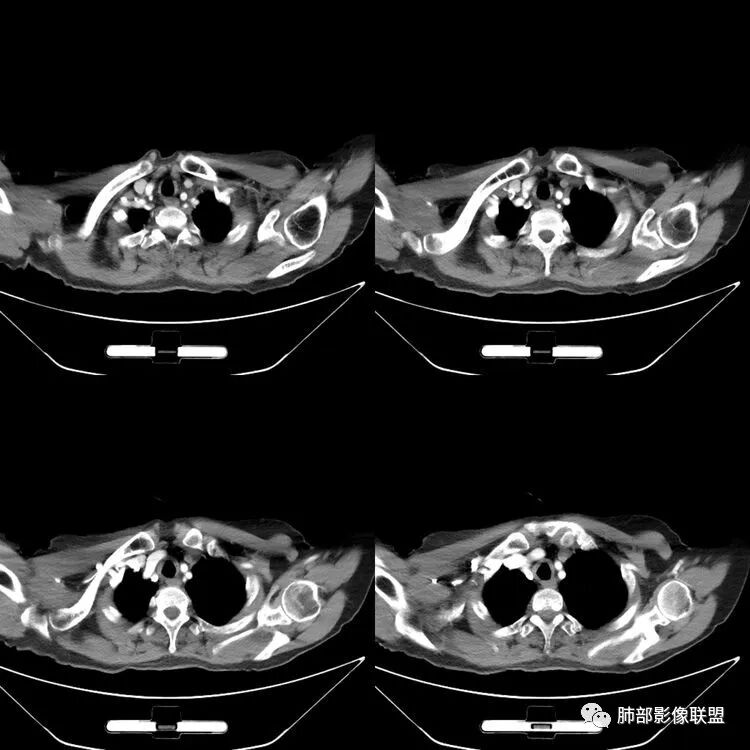

患者,女,64岁,反复咳嗽、咳痰、胸闷10年,加重2周患者10余年来每当受凉感冒出现咳嗽、咳痰、胸闷,有时痰中带血,输液治疗(具体不详)可好转。既往有声带肥厚手术病史。CT示气管、主支气管及分支支气管管壁弥漫性增厚累及膜部,局部伴钙化,管腔狭窄,考虑淀粉样变性

患者,女,64岁,反复咳嗽、咳痰、胸闷10年,加重2周。气管支气管及两肺下叶 支气管弥漫性的环状增厚,管腔扩张,管腔感觉比较松弛。第一感觉,气管支气管淀粉样变。鉴别诊断,1、支气管内膜结核,肺内散在一些支气管的播散病灶,粟粒结节为主,形态比较单一。2、复发性的多软骨炎,就得了解一下其他部位,有没有多个部位的软骨炎。这个病人右侧胸廓缩小,升主动脉明显的扩张,其横径明显的超过了降主动脉。

征象很明确

弥漫支气管壁增厚,膜部受累

声带肥厚——受累

隐约见钙化

南边:肺部有肺气肿支气管腔狭窄淀粉样变性?复发性多软骨炎?血管炎?慢支?结核?曲霉菌?南边:一般还是淀粉样变性与复发性多软骨炎鉴别其次就是支气管骨化症,但是骨化下朝上,且壁结节状钙化明显,本例不太支持。至于结核、曲霉菌?1.结核,一般不会这么广泛,支气管壁狭窄后扩张2.曲霉菌可以这么广泛,但是支气管壁管腔扩张,而且附近脂肪间隙有炎性反应,不太支持;3.血管炎,一般合并肺内有病灶,但是声带受累,放待排;4.软骨炎一般全身受累,例如耳廓等;而且膜部不受累,不太支持;倾向于淀粉样变性;淀粉分很多型,气管支气管是最常见的。尘缘:影像上生理性钙化与支气管骨化无法区别,镜检也不好鉴别,需要依赖活检,看粘膜中是否合并炎性改变(淋巴细胞,组织细胞等炎性细胞侵润)来鉴别Coke with ice:经常看到的这种是老年性肺改变,又称年龄相关肺改变。气管和支气管弥漫性软骨钙化,常见老年女性。尘缘:支气管骨化症很罕见的,所以绝大多数还是生理性钙化。对于老年人,无临床症状的钙化,还是基本上都是生理性钙化,无临床意义。大雄:如果管壁钙化伴明显增厚 影像还是提示一下建议支气管镜稳妥些

病理结果:肺淀粉样变

气管支气管淀粉样变性

三、影像表现

1.气管支气管型

①气管支气管壁增厚,形成粘膜下斑块与结节

②管腔广泛狭窄、闭塞

③管壁钙化

④膜部受累(具有重要鉴别意义)